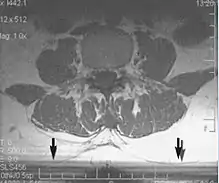

Flow can manifest as either an altered intravascular signal (flow enhancement or flow-related signal loss), or as flow-related artifacts (ghost images or spatial misregistration). Flow enhancement, also known as inflow effect, is caused by fully magnetised protons entering the imaged slice while the stationary protons have not fully regained their magnetization.[1] The fully magnetized protons yield a high signal in comparison with the rest of the surroundings. High velocity flow causes the protons entering the image to be removed from it by the time the 180-degree pulse is administered. The effect is that these protons do not contribute to the echo and are registered as a signal void or flow-related signal loss (Fig. 2).[1] Spatial misregistration manifests as displacement of an intravascular signal owing to position encoding of a voxel in the phase direction preceding frequency encoding by time TE/2.The intensity of the artifact is dependent on the signal intensity from the vessel, and is less apparent with increased TE.[1]